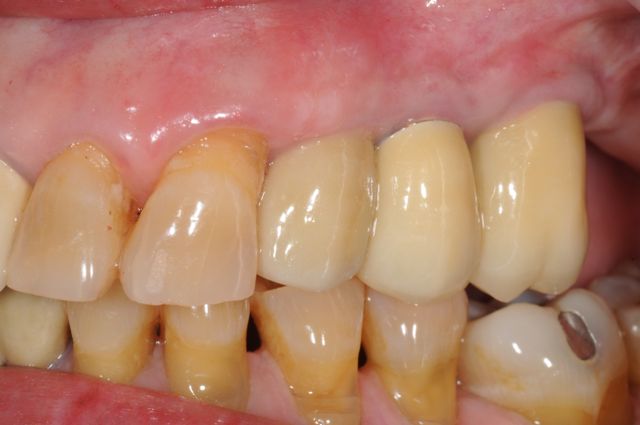

A Staged extraction, sinus lift bone graft, and three dental implants for replacement of teeth in a partially edentulous patient.